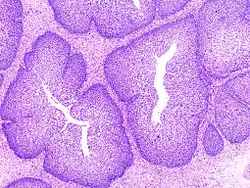

Brodawczak odwrócony wyścielony jest nabłonkiem wielowarstwowym płaskim lub cylindrycznym, który rozrasta się w głąb błony śluzowej i dalej penetruje palczastymi wypustkami w kierunku światła zatok przynosowych (wzrost endofityczny). Taki typ wzrostu odróżnia go od wzrostu typowych brodawczaków, które rosną w kierunku zewnętrznej powierzchni narządu (egzofitycznie), stąd jego nazwa "odwrócony". Brodawczak odwrócony rozrastając się niszczy kość. Ma on wygląd kruchego, policyklicznego guza barwy szaroróżowej o nierównej powierzchni, który wypełnia jamę nosową oraz zatoki przynosowe. Nabłonek wielowarstwowy płaski pokrywający guz jest dojrzały. Spoczywa on na błonie podstawnej, która oddziela go od łącznotkankowego zrębiu. Soplowate wypustki nabłonkowe licznie się rozgałęziają w łącznotkankowym zrębie. W środku palczastych wypustek występują zwykle torbielowate przestrzenie wypełnione śluzem.